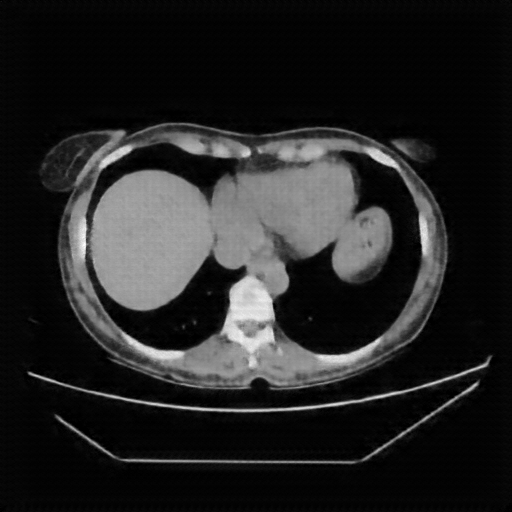

Image Grid

4Γ—3 grid: Rows show different image types (Original NATIVE, Reconstructed NATIVE, Original VENOUS, Generated VENOUS), Columns show windowing techniques (No Window, Lung Window, Mediastinum Window)

Reconstructed NATIVE CT scan (cycle consistency)

Full window (WL 1023.5, WW 4095 β†’ Low βˆ’1024, High +3071)

Lung window (WL -600, WW 1500 β†’ Low βˆ’1350, High +150)

Mediastinum window (WL 40, WW 400 β†’ Low βˆ’160, High +240)